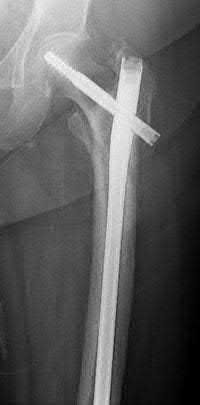

What is the most common type of malalignment after intramedullary nailing of distal 1/3 extra-articular tibia fractures using a infrapatellar approach when compared with plating?

The most common type of malalignment after intramedullary nailing of distal 1/3 extra-articular tibia fractures using an infrapatellar approach when compared with plating is valgus malalignment.

Fixation of distal one-third tibial shaft fractures can be successfully treated with either intramedullary nailing or plating. The literature describes advantages and disadvantages to both approaches, however intramedullary nailing has been shown to lead to increased rates of valgus malunion. Recent studies have shown that using a suprapatellar approach may decrease the incidence of valgus malalignement.

Vallier et al performed a randomized prospective study to compare plate and nail stabilization for distal tibia shaft fractures by assessing complications and secondary procedures. One-hundred and four patients were randomized to either reamed intramedullary nailing, or medial distal tibia plate fixation.

Primary angular malalignment was identified in 17 patients (16.3%). This included four patients treated with tibial plating (8.3%) and 13 patients treated with nails (23%, P = 0.02). Eight of these (7.7% of all patients) had malalignment between 6° and 10° of angulation. Valgus was the most common

angular deformity, accounting for 70% of angular deformity cases.

Avilucea et al. looked at the immediate postoperative alignment of distal tibia fractures (within 5 cm of the tibial plafond) treated with suprapatellar intramedullary nail (IMN) insertion compared with the infrapatellar technique. They found primary angular malalignment of ≥5 degrees occurred in 35 (26.1%) patients with infrapatellar IMN insertion and in 5 (3.8%) patients who underwent suprapatellar IMN insertion. They conclude suprapatellar IMN technique results in a significantly lower rate of malalignment compared with the infrapatellar IMN technique.